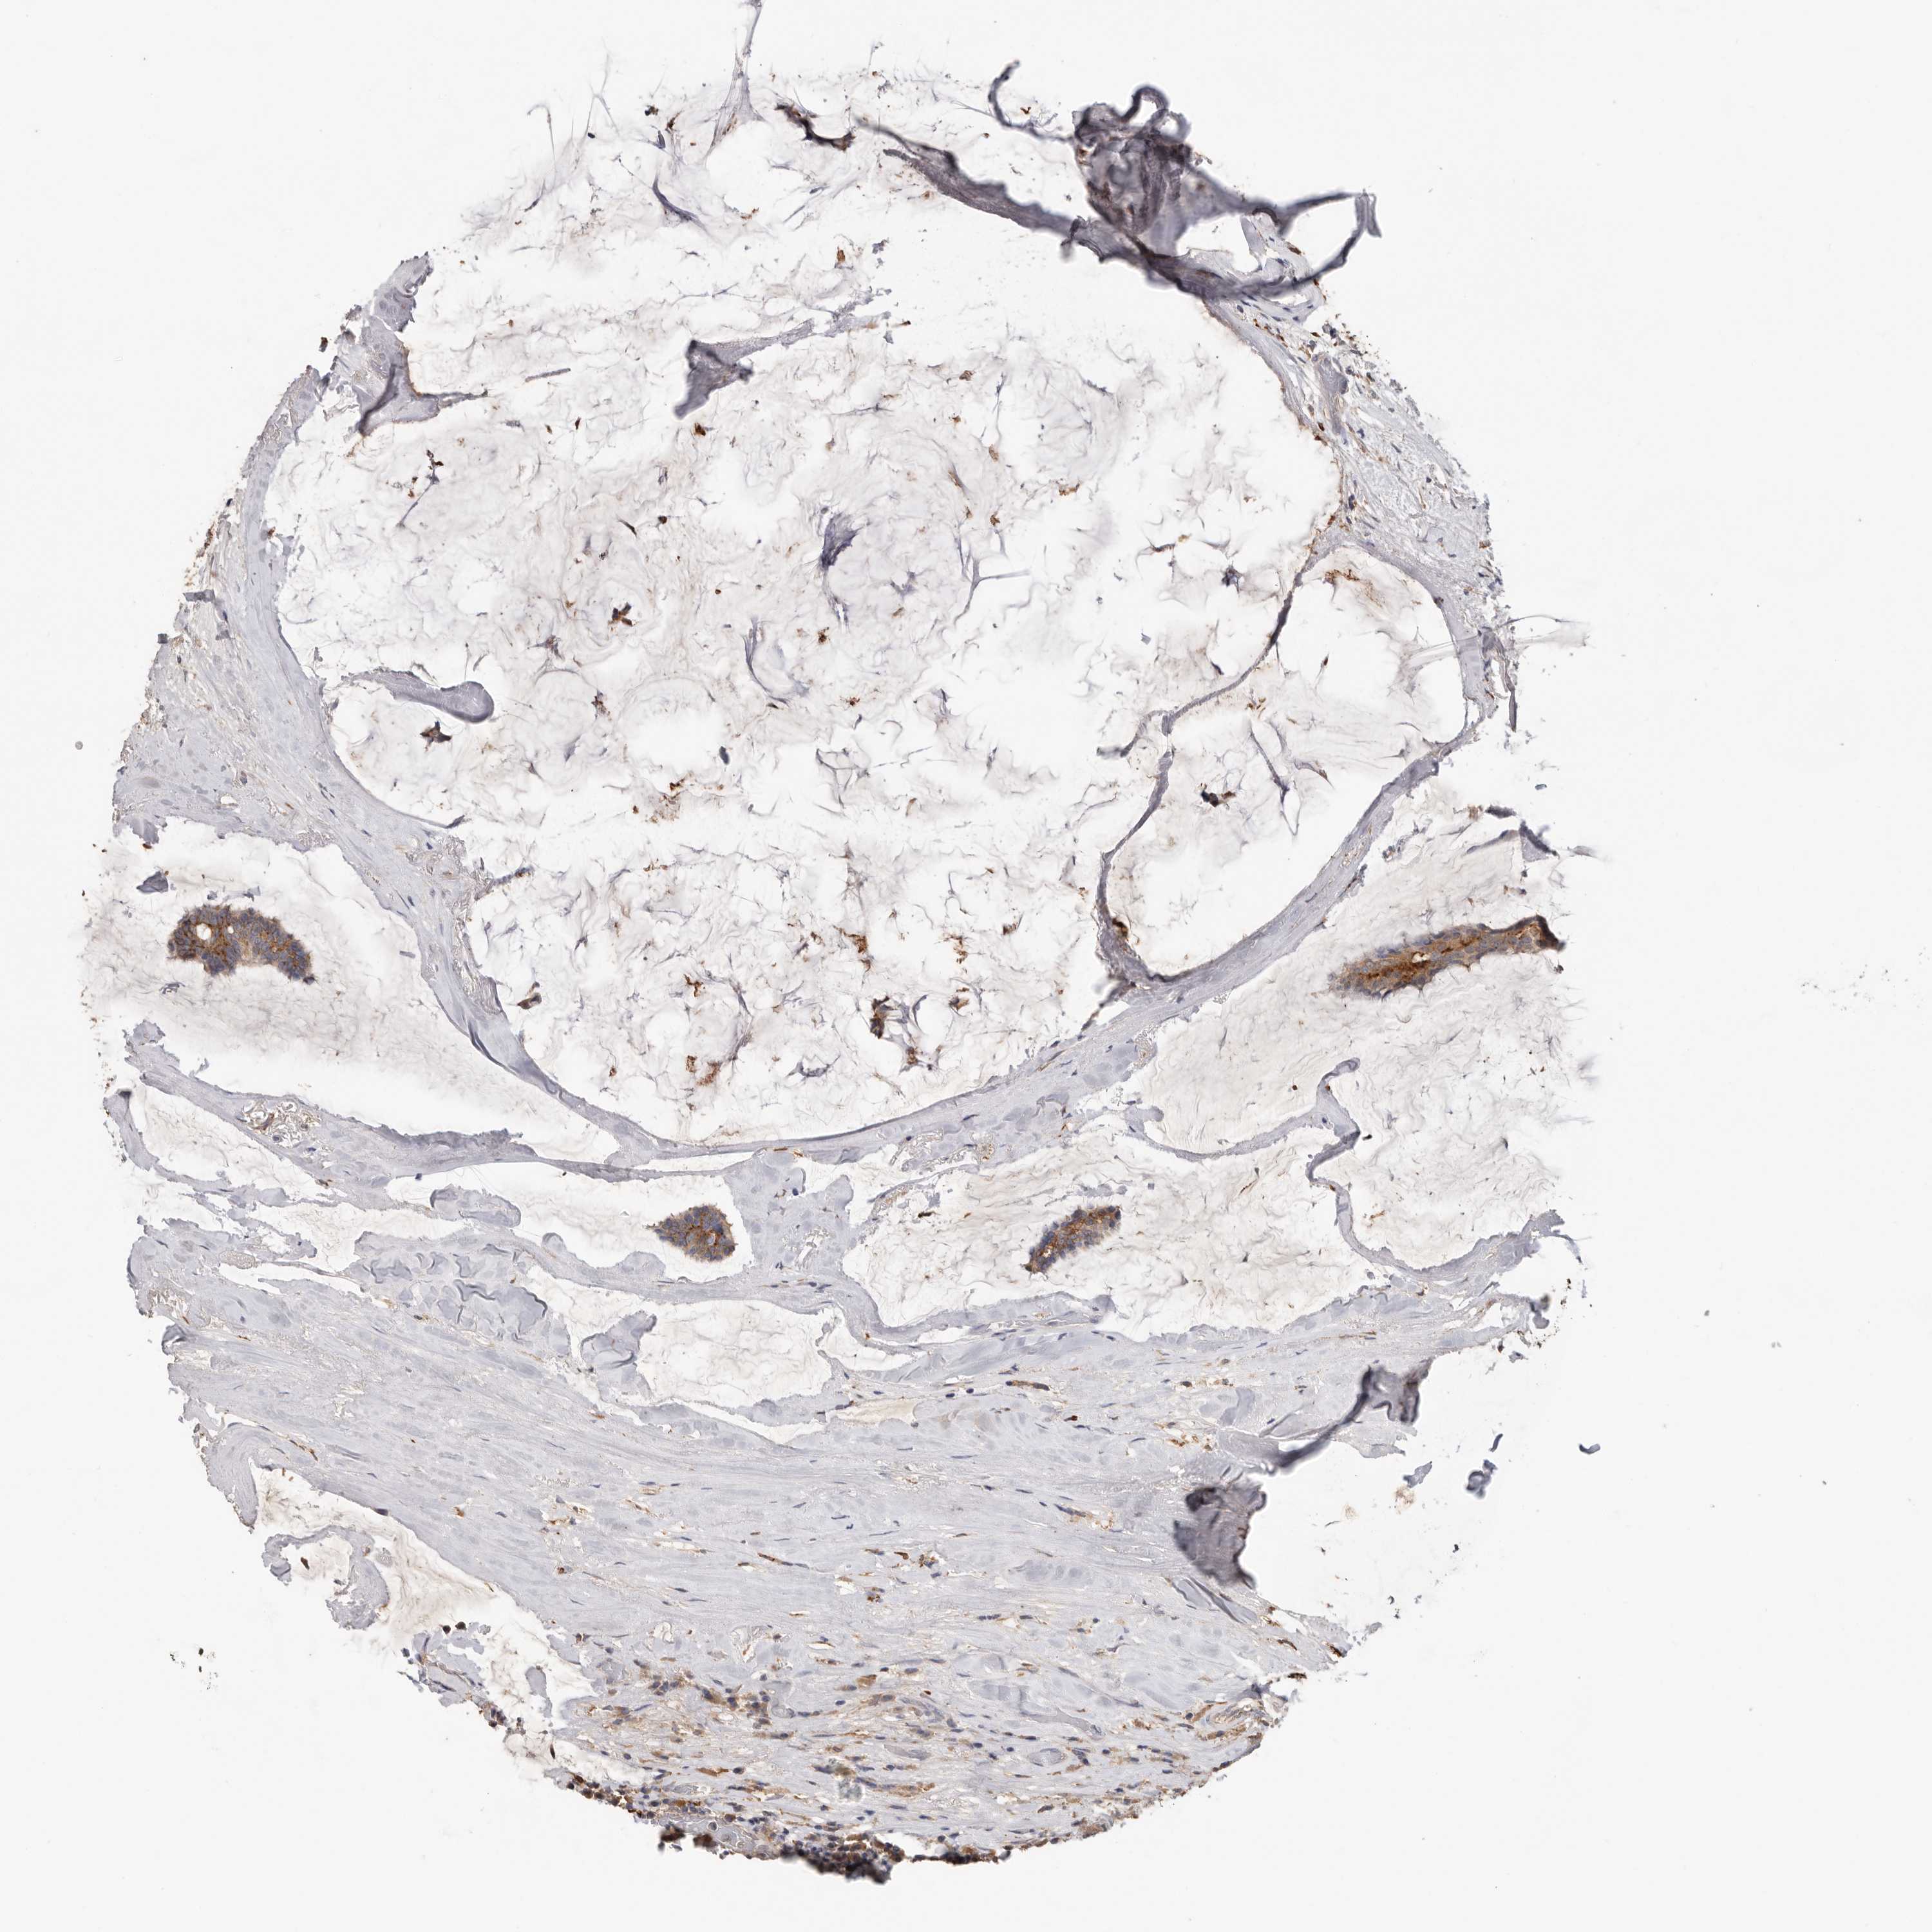

Breast cancer

Human cancer